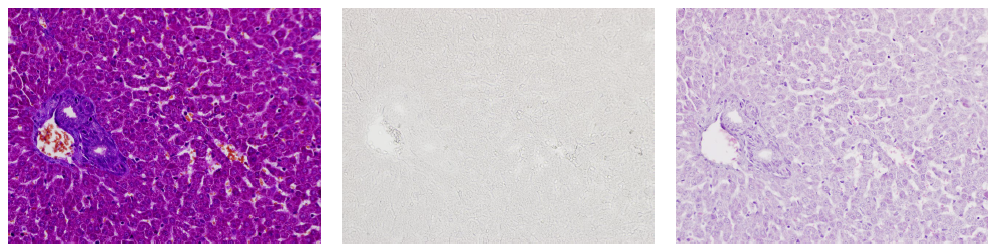

使用小(xiǎo)鼠肝髒标本進行(xíng)MT染色時(shí)

使用deColorizing Solution 1和(hé)2進行(xíng)脫色

左至右:MT染色→脫色→HE染色

(數(shù)據提供:麻布大(dà)學小(xiǎo)澤秋沙先生(shēng)、坂上(shàng)元榮先生(shēng))